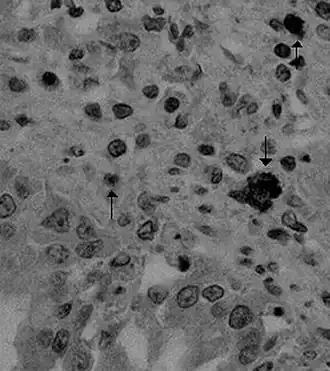

- ↑ (en) Zook, King, Robison et McCombs, « Ultrastructural evidence for the viral etiology of feline infectious peritonitis », Pathologia veterinaria, vol. 5, no 1, , p. 91–95 (DOI 10.1177/030098586800500112, lire en ligne)